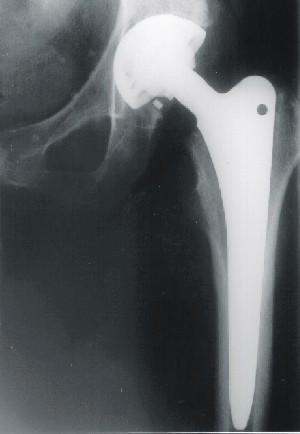

Rheuma, Arthrose oder ein Unfall: die Ursachen, die eine Hüftgelenksoperation notwendig machen können, sind vielfältig. Die einzige Lösung besteht in vielen Fällen darin, ein künstliches Hüftgelenk einzusetzen.

können. Aus diesem Grunde werden bei diesen Hüftgelenksoperationen neben den normalen Röntgenbildern auch viele Computertomografie-Aufnahmen gemacht, die die notwendige räumliche Ansicht der Hüfte ermöglichen. Der Nachteil: die Strahlenbelastung des Patienten in der Hüftregion ist durch die CT-Aufnahmen relativ hoch, eine Schädigung der Erbinformationen ist somit nicht auszuschließen. Dieser Nachteil ist um so besorgniserregender, da das Alter der Hüftgelenkspatienten zunehmend sinkt, und somit gerade junge Frauen einer großen Gefahr ausgesetzt sind.

Im Rahmen eines Projekts zur Verbesserung der Hüftgelenksoperationen arbeitet die Technologietransferstelle der FH Worms unter der Leitung des Autors daran, eine räumliche Ansicht der Hüfte bei deutlich verringertem Strahlenrisiko für den Patienten möglich zu machen. Dabei werden nur zwei Röntgenaufnahmen der Hüfte aus unterschiedlichen Perspektiven gebraucht. Die dahinter stehende Idee ist dem menschlichen Sehen nachempfunden.